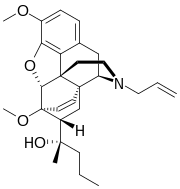

Oripavine derivatives

Thienorphine

- 7-PET

- Acetorphine

- Alletorphine (N-allyl-noretorphine)

- BU-48

- Buprenorphine

- Buprenorphine-3-glucuronide

- Cyprenorphine

- Dihydroetorphine

- Etorphine

- Homprenorphine

- 18,19-Dehydrobuprenorphine (HS-599)

- N-cyclopropylmethylnoretorphine

- Nepenthone

- Norbuprenorphine

- Norbuprenorphine-3-glucuronide

- Thevinone

- Thienorphine

Structures

| Oripavine derivatives | ||||

7-PET 7-PET |

Acetorphine Acetorphine |

Alletorphine Alletorphine |

BU-48 BU-48 |

Buprenorphine Buprenorphine |

Cyprenorphine Cyprenorphine |

Dihydroetorphine Dihydroetorphine |

Etorphine Etorphine |

Homprenorphine Homprenorphine |

18,19-Dehydrobuprenorphine 18,19-Dehydrobuprenorphine |

N-cyclopropylmethylnoretorphine N-cyclopropylmethylnoretorphine |

Nepenthone Nepenthone |

Norbuprenorphine Norbuprenorphine |

Thevinone Thevinone |

Thienorphine Thienorphine |